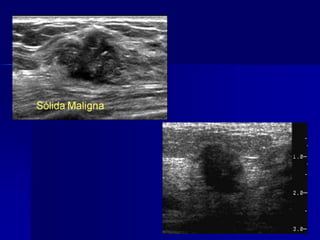

Sólida benigna y maligna

Benigna o maligna

 Sólida

 Quística

Fibroadenoma

Neoplasia Maligna

(Ca y otras)

Quiste mamario

(Raro Ca intraquístico)

Benigna o maligna Sólida  Quística Fibroadenoma Neoplasia Maligna (Ca y otras) Quiste mamario (Raro Ca intraquístico)